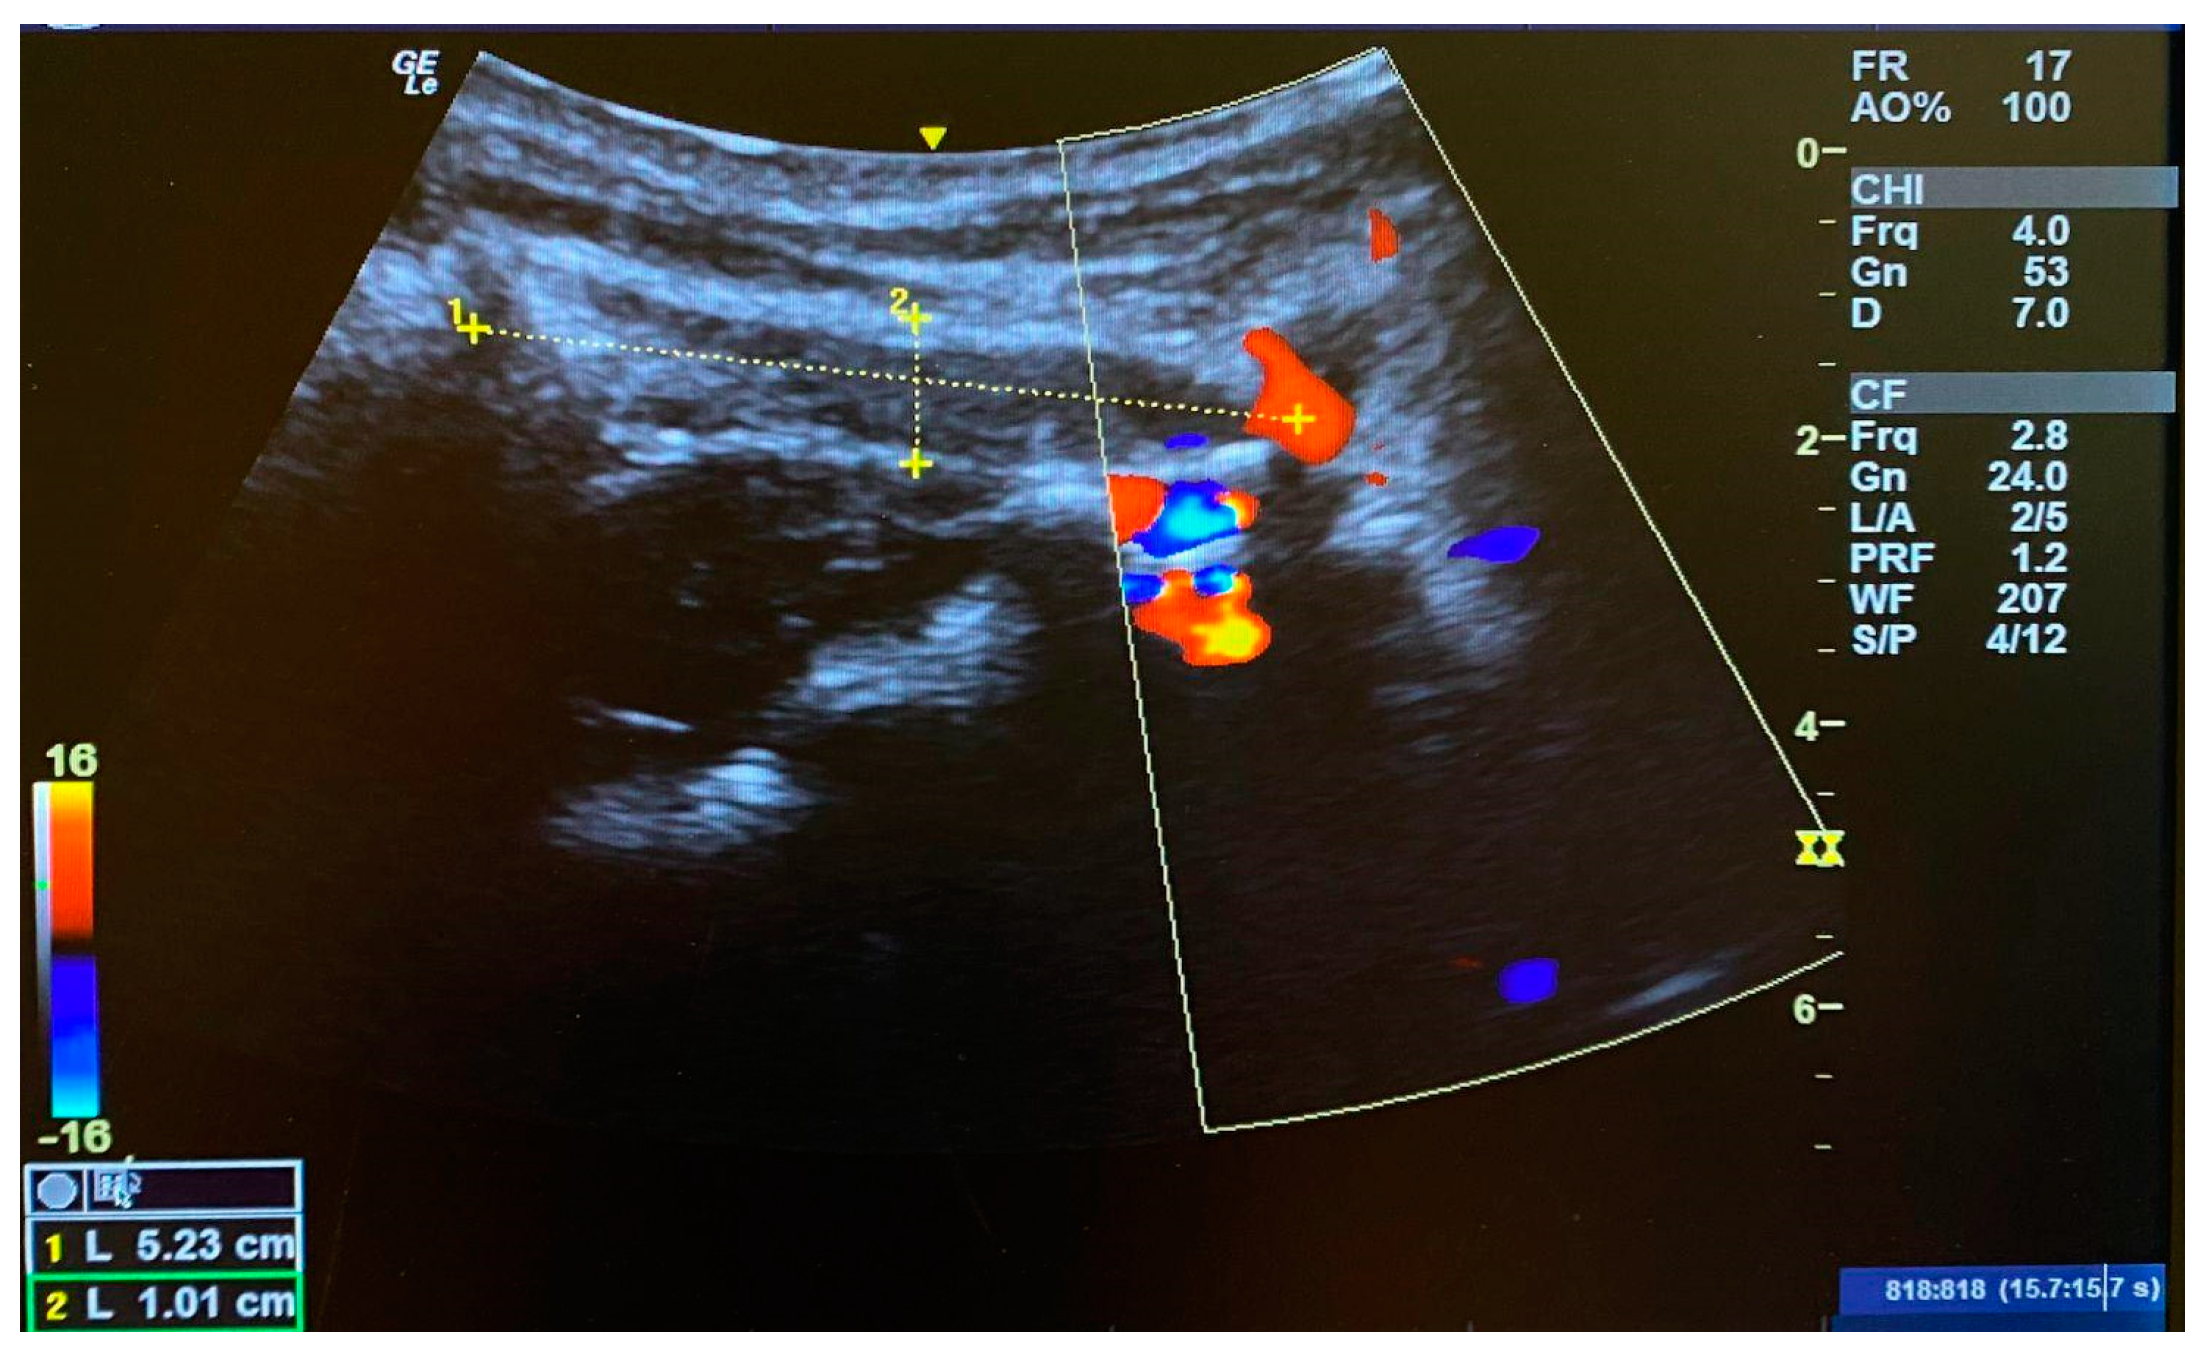

2.2. Study Protocol

- Fernandez-de-Las-Penas, C.; Mesa-Jimenez, J.A.; Lopez-Davis, A.; Koppenhaver, S.L.; Arias-Buria, J.L. Cadaveric and ultrasonographic validation of needling placement in the obliquus capitis inferior muscle. Musculoskelet. Sci. Pract. 2020, 45, 102075. [Google Scholar] [CrossRef] [PubMed]